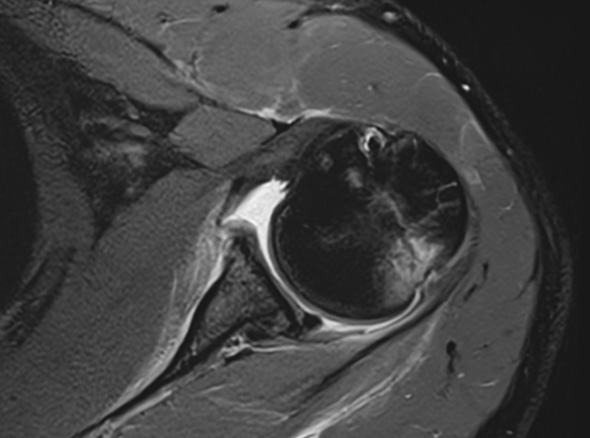

어깨가 가볍게 빠지는 증상, 어깨와 팔꿈치 사이에 있는

상완골이 어깨뼈에서 빠져나오는 증상을 어깨 탈구라고 합니다.

상완골두의 울타리 역할을 하는

관절와순 순상이 동반되는 경우도 있습니다.